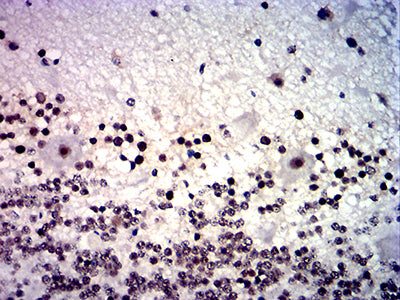

分类: 科研抗体货号: 31874别名: NMYC; ODED; MODED; N-myc; bHLHe37应用: IHC,FCM反应种属: Human